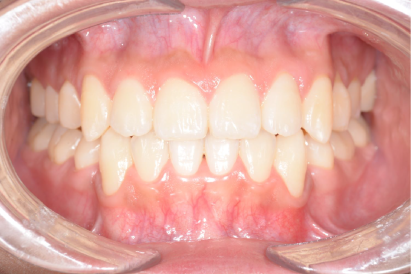

術後

年代、性別

30代、女性

職業

会社役員

主訴

奥歯の詰め物が頻繫に取れる

部位

インビザラインによる全顎矯正と上下顎奥歯8本のセラミック治療

治療期間

1年6ヶ月

矯正費用

95万円

施術説明

患者は10年ほど前に矯正治療の既往がありました。歯並び自体は綺麗になったものの、矯正後に奥歯の詰め物が頻繁に外れて虫歯になり、総合的な治療を希望して来院されました。診察の結果、矯正治療をしているにも関わらず、前歯が噛んでいないので奥歯に過剰な咬合負荷がかかっていることがわかりました。そのため、前歯を咬合させ、奥歯が干渉しないように再度の矯正と奥歯の修復治療が必要と判断しました。治療後には、審美的にも機能的にも満足して頂き、問題なく生活できるようになりました。このような治療は矯正専門医でなくては不可能です。歯のトラブルと歯並びが複合する問題は、複数の専門医が所属する医院を受診して下さい。

副作用・リスク

なし